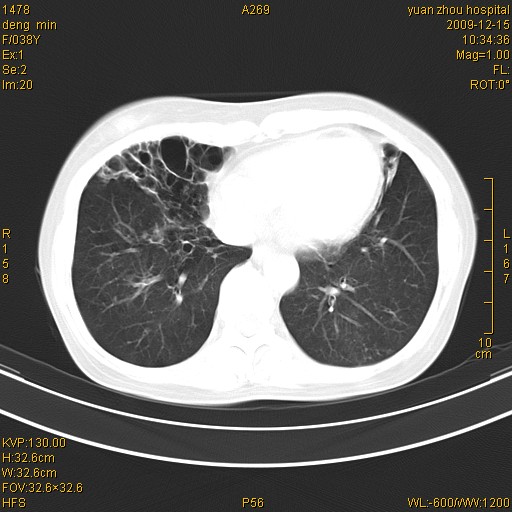

标题: CT23919:F38Y 咳嗽月余 [打印本页]

标题: CT23919:F38Y 咳嗽月余

右肺中下叶、左肺上叶舌段及左肺下叶支气管扩张合并感染。